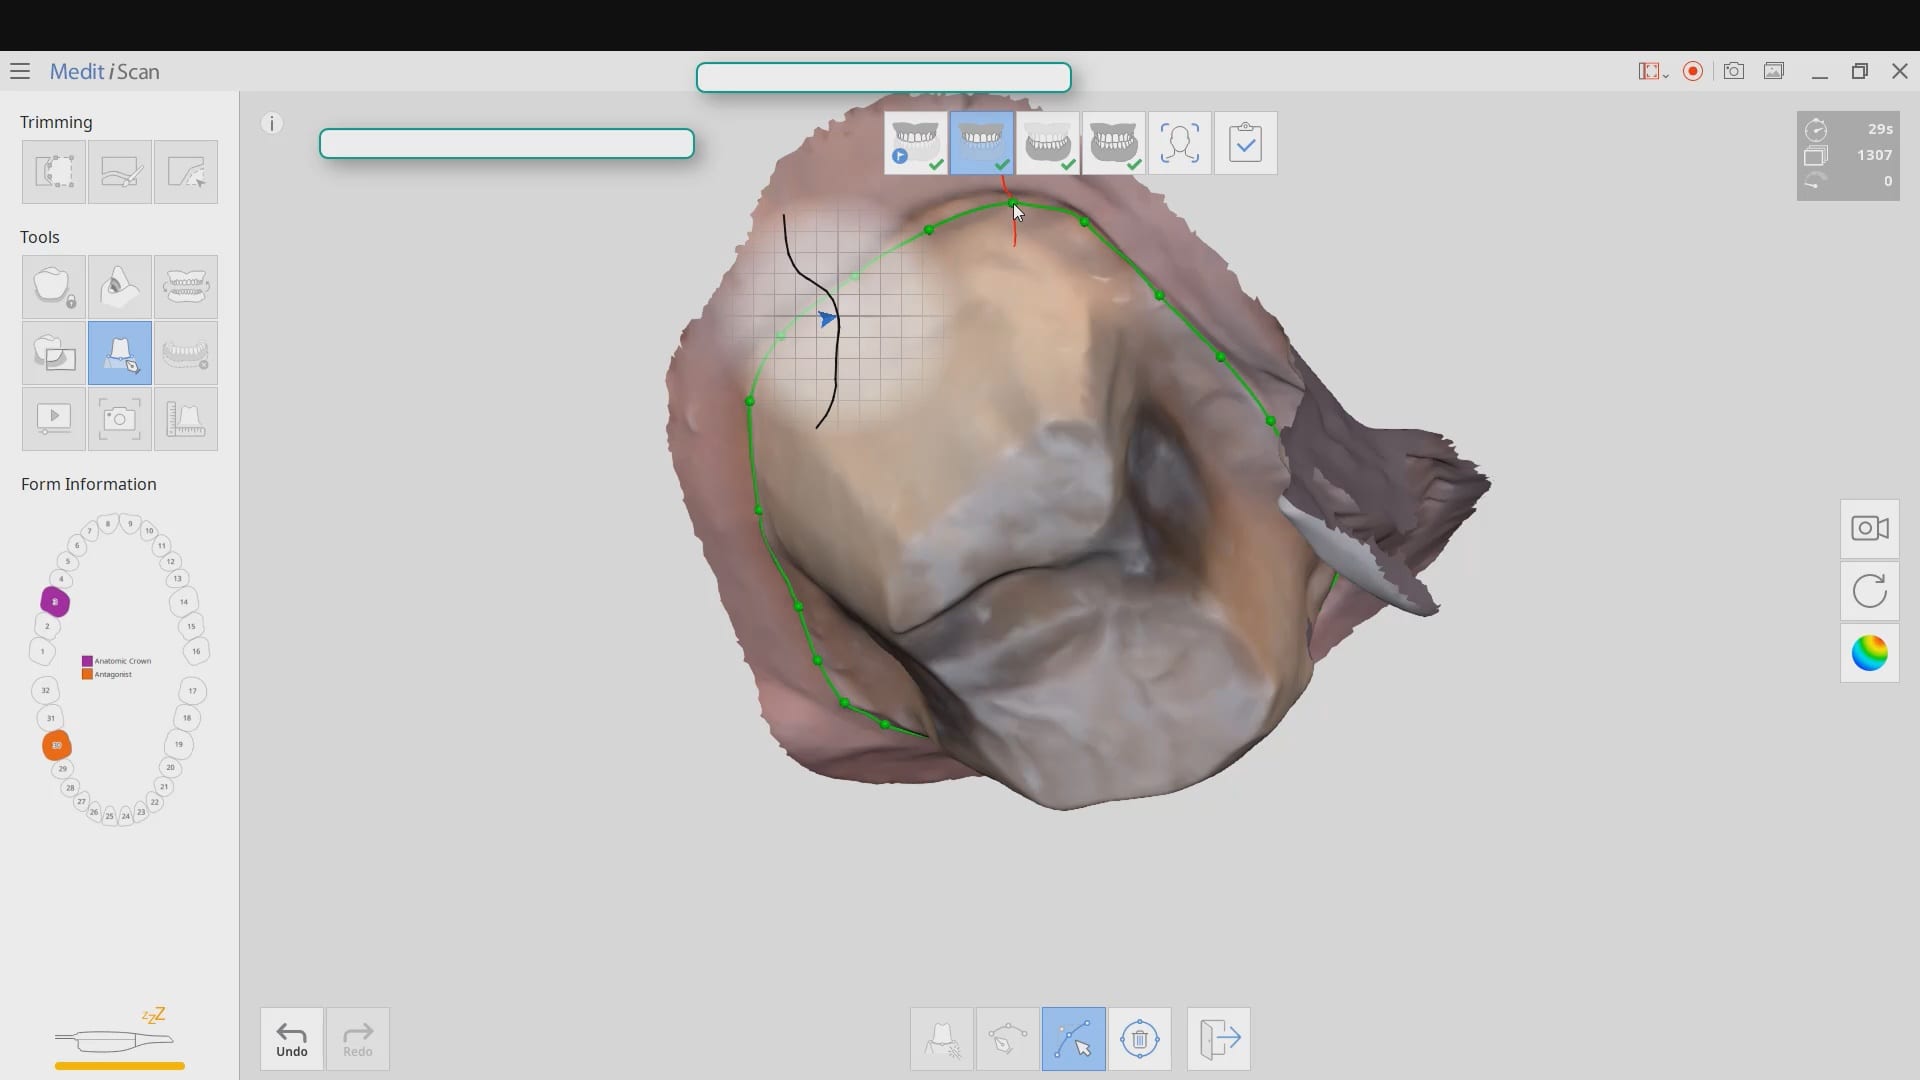

March 9, 2020Most manufacturers recommend that you start your imaging at the second molar area, which is the least practical area to start with. The tongue and the lip and saliva are […]